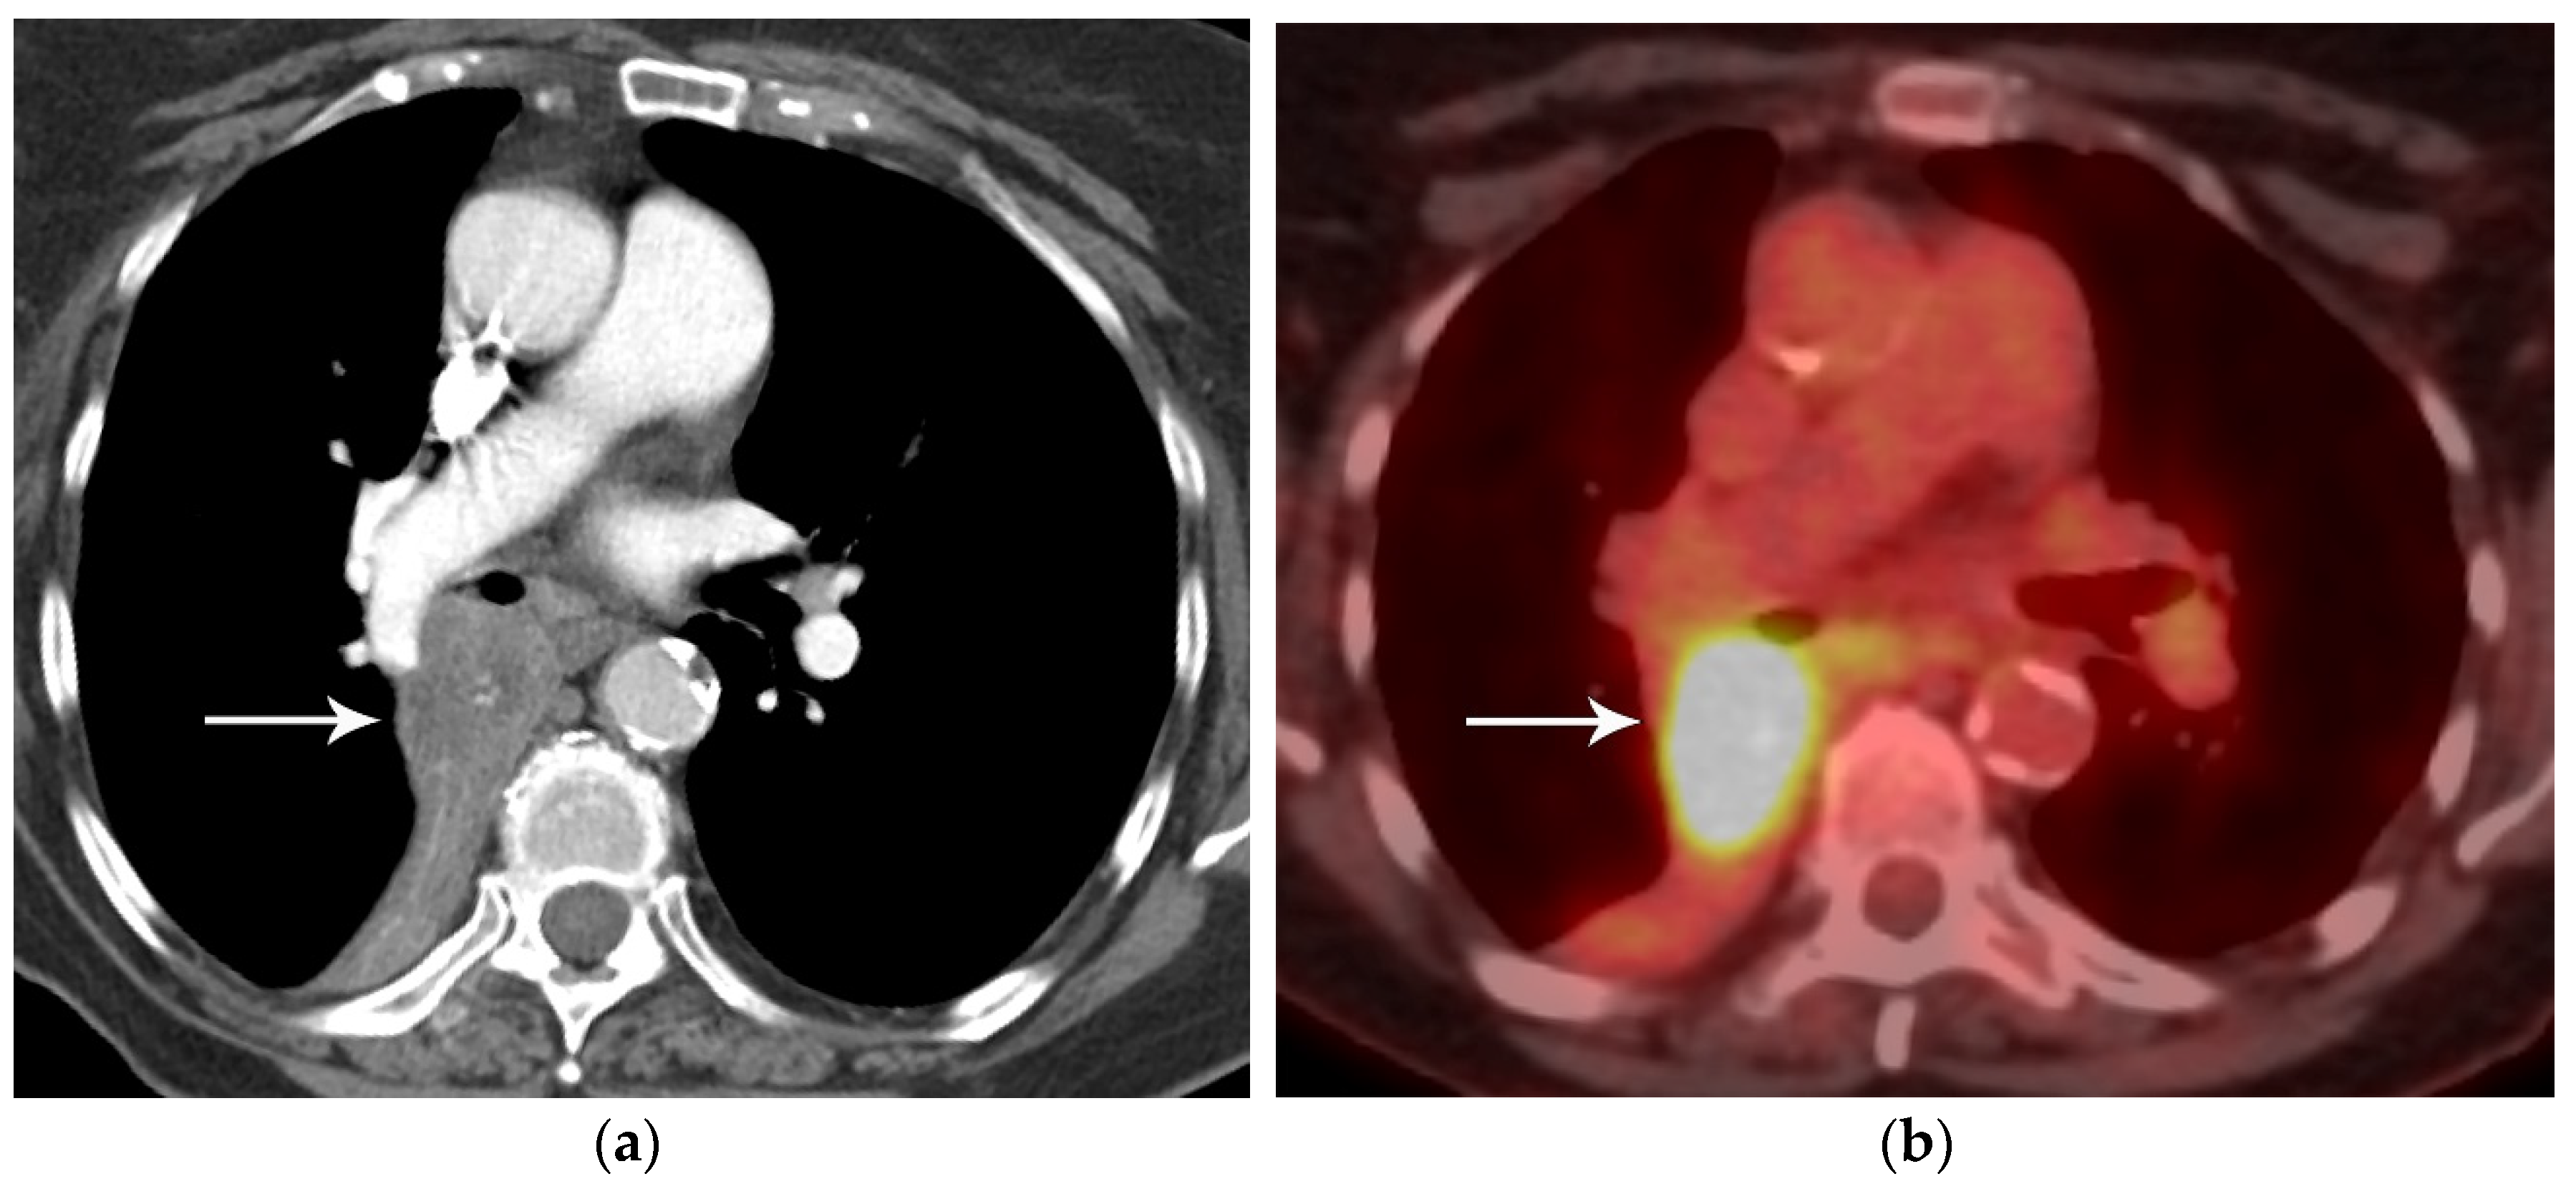

4. M Classification